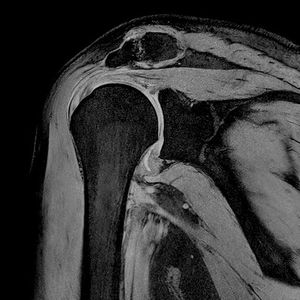

Terra7 MSK morphology imaging

High resolution imaging offers potential for clinical applications in orthopedics where the details make a difference. Shoulder, knee, ankle, hand, and foot imaging of joints and cartilage help improve diagnostics.